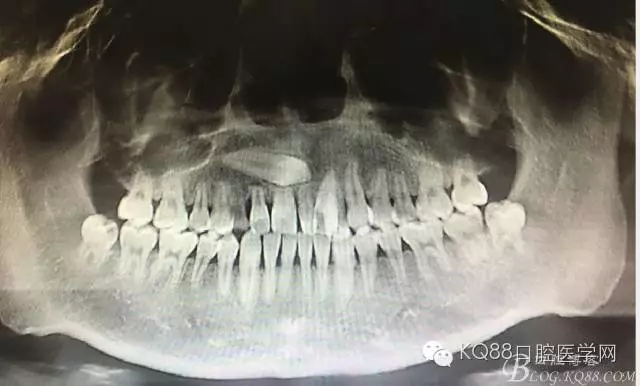

患者、田xx、女、17歲、主訴:右側(cè)門牙松動(dòng),要求治療。??茩z查:11松動(dòng)Ⅰ度,11與21之間有一多生牙,CBCT檢查:13位于11根尖區(qū),并壓迫11牙根吸收約1/2,53滯留、正畸科建議:拔除11、并正畸牽引13到11位置,然后行13牙冠改形。患者不同意該方案,僅考慮拔除13,防止11牙根進(jìn)一步吸收。醫(yī)患溝通后,同意患者的要求、拔除埋伏13,簽知情同意書。

圖2. CBCT檢查:13橫位埋伏阻生、導(dǎo)致11牙根吸收約1/2.

圖3.CBCT的影像檢查資料:矢狀面13牙冠壓迫11牙根吸收約1/2,并且確定13牙冠靠近唇側(cè),手術(shù)入路定在唇側(cè)